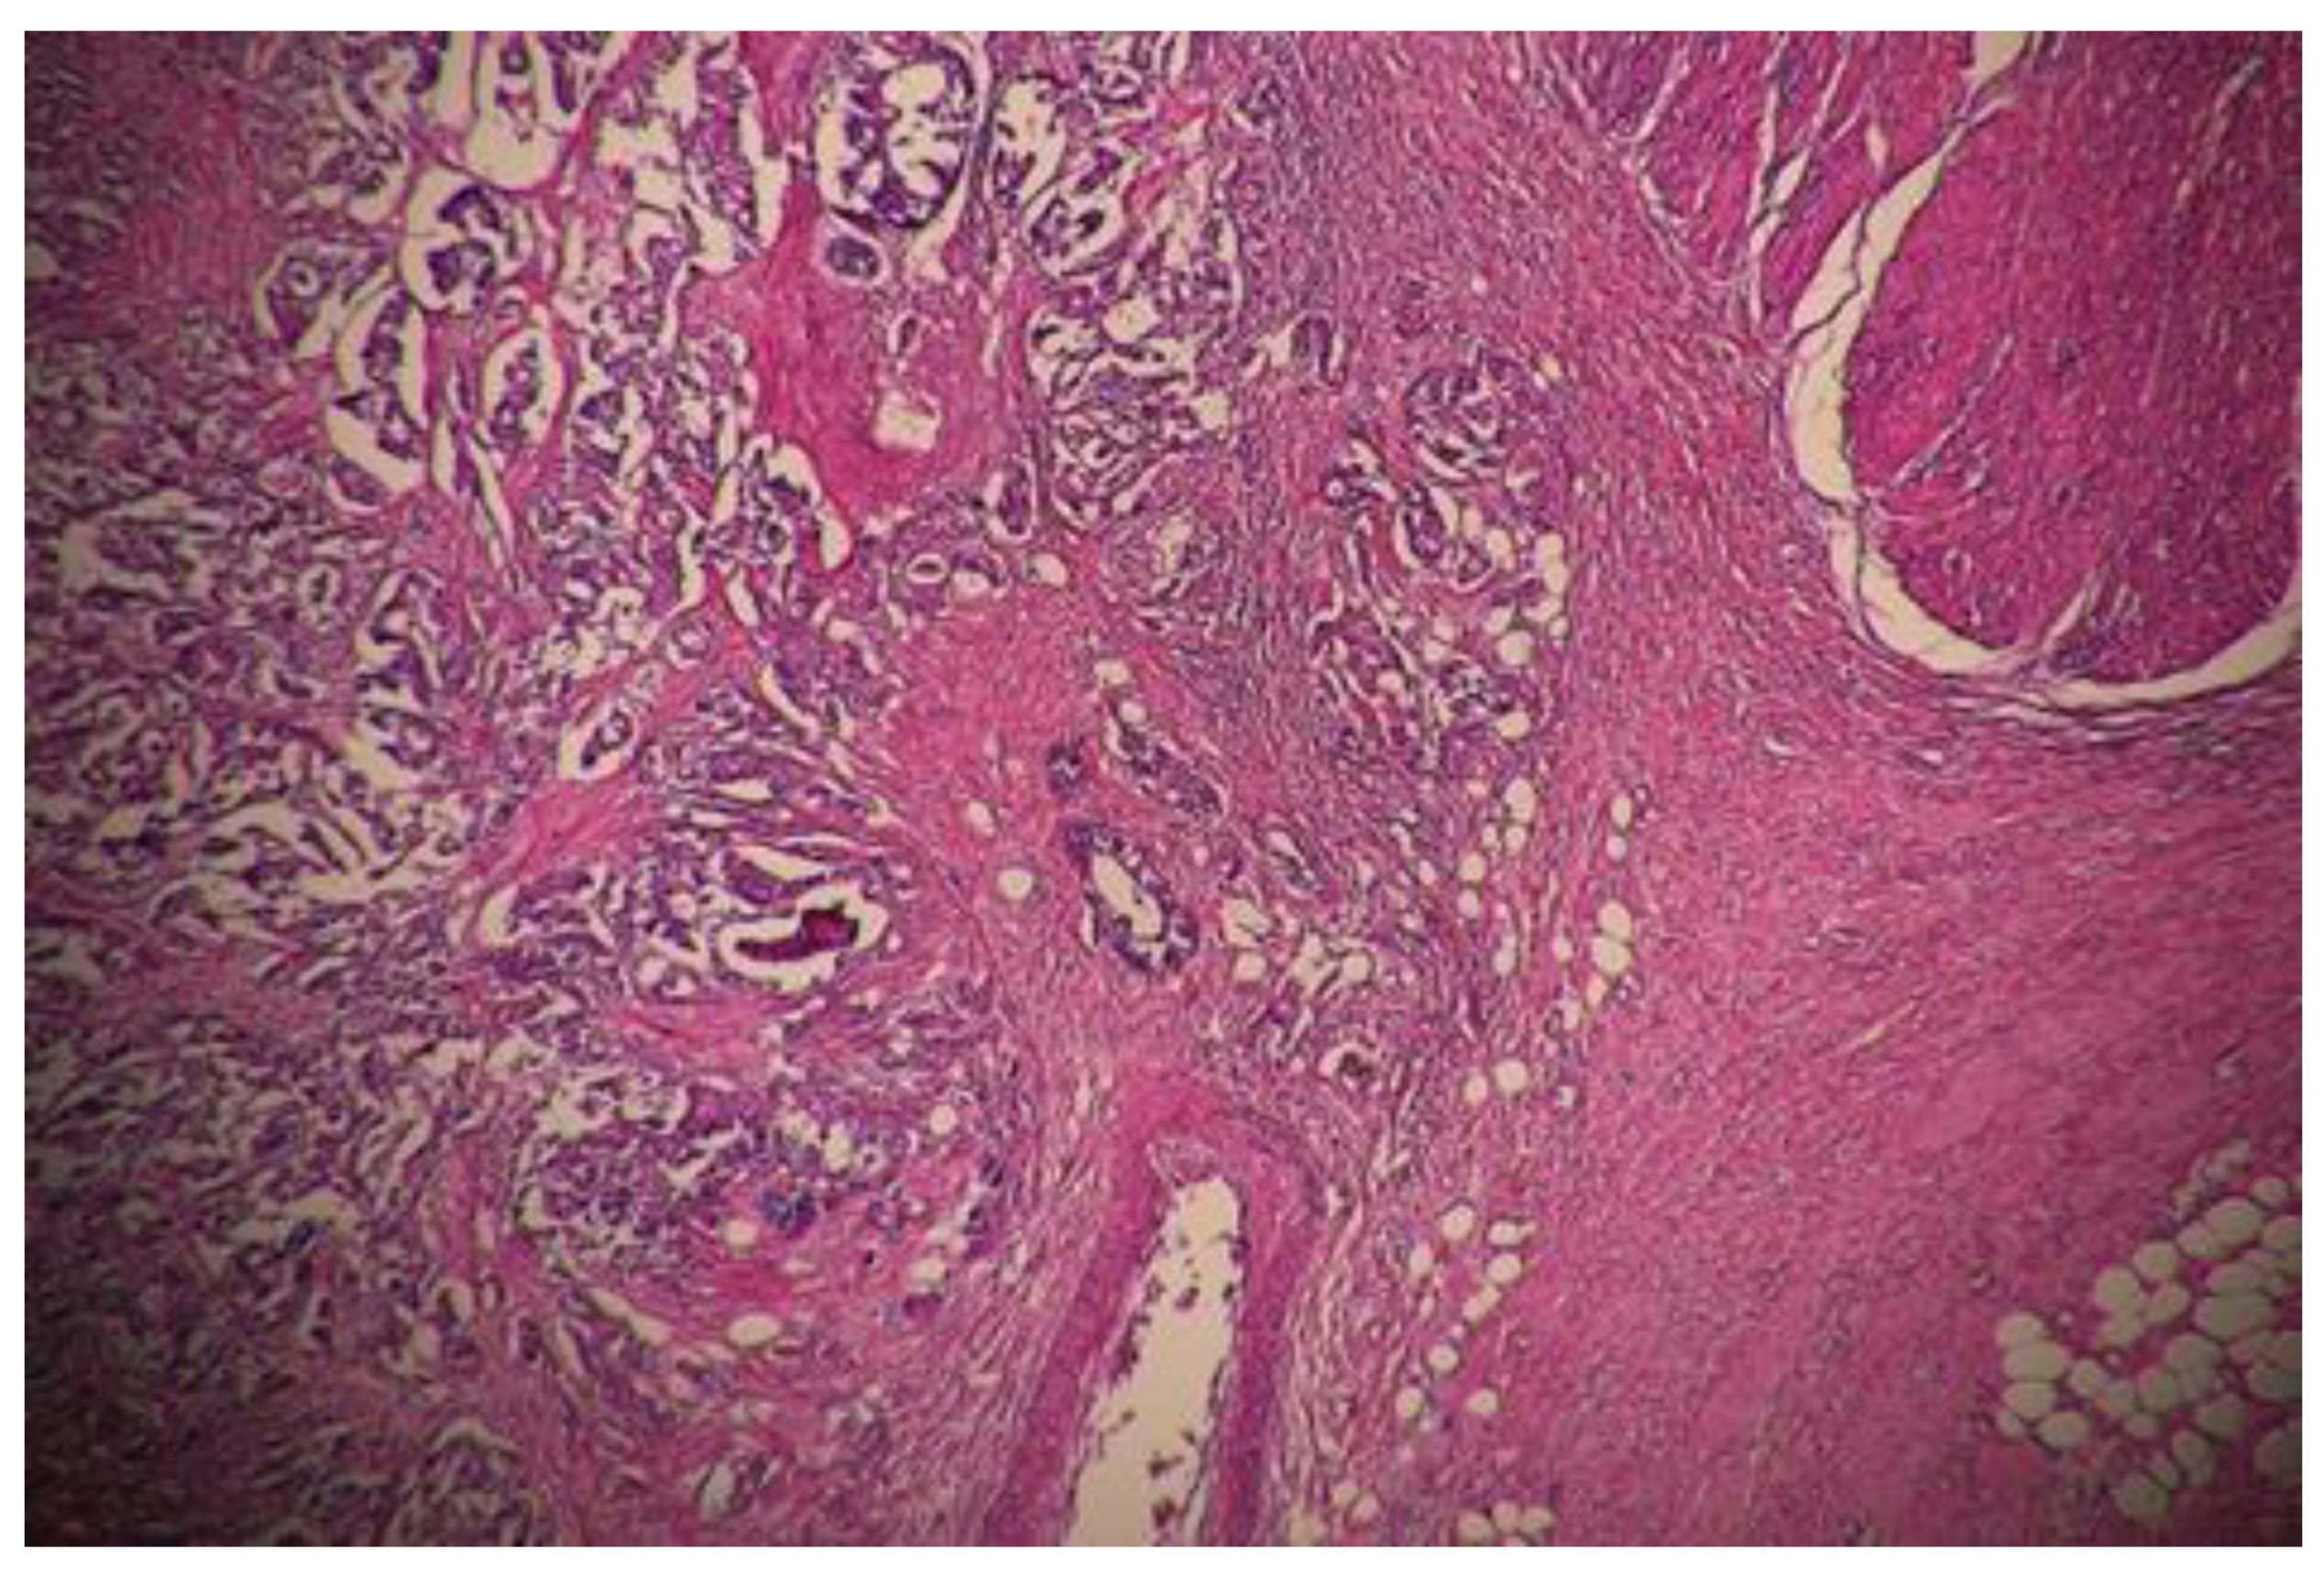

- Dworak, O.; Keilholz, L.; Hoffmann, A. Pathological features of rectal cancer after preoperative radiochemotherapy. Int. J. Color. Dis. 1997, 12, 19–23. [Google Scholar] [CrossRef] [PubMed]

- Ryan, R.; Gibbons, D.; Hyland, J.M.; Treanor, D.; White, A.; Mulcahy, H.E.; O’Donoghue, D.P.; Moriarty, M.; Fennelly, D.; Sheahan, K. Pathological response following long-course neoadjuvant chemoradiotherapy for locally advanced rectal cancer. Histopathology 2005, 47, 141–146. [Google Scholar] [CrossRef]

- Chen, H.Y.; Feng, L.L.; Li, M.; Ju, H.Q.; Ding, Y.; Lan, M.; Song, S.M.; Han, W.D.; Yu, L.; Wei, M.B.; et al. College of American Pathologists Tumor Regression Grading System for Long-Term Outcome in Patients with Locally Advanced Rectal Cancer. Oncologist 2021, 26, e780–e793. [Google Scholar] [CrossRef] [PubMed]